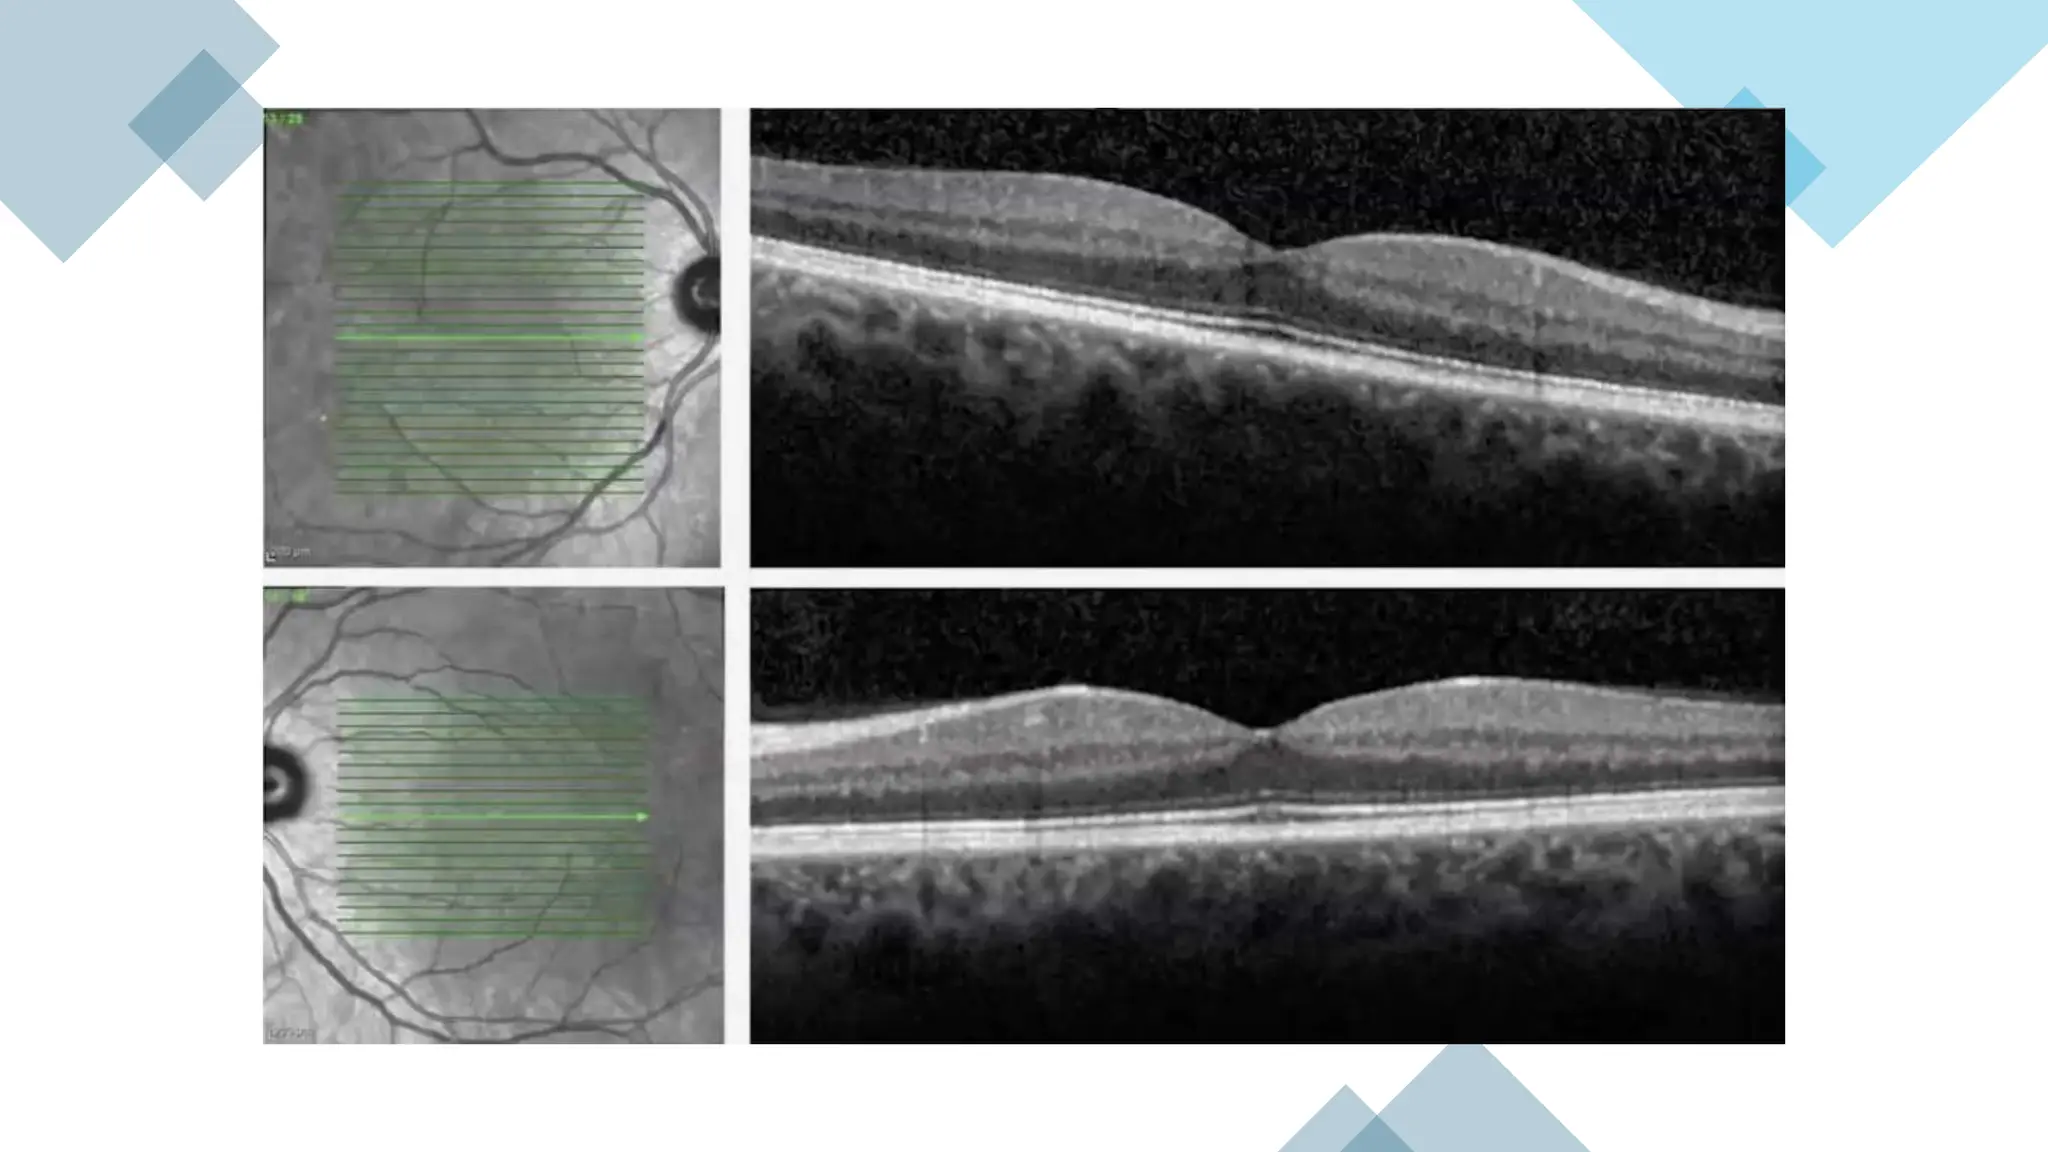

DISORGANIZATIO

N OF INTERNAL

RETINAL LAYERS

D R I L

DISORGANIZATION

OF OUTER RETINAL

LAYERS

D R O L

• #20 Disruption ilm, photors

• #21 DROL DRIL